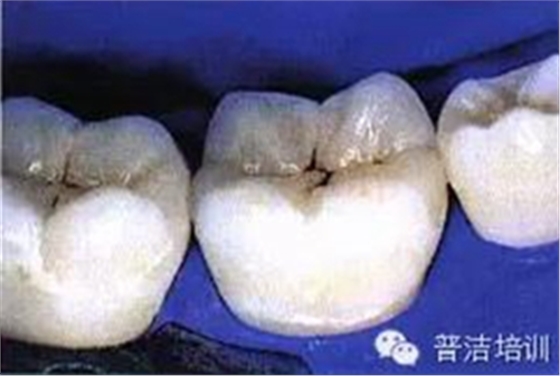

十六、最終的修復(fù)體,是不是很漂亮

修復(fù)后一周復(fù)查